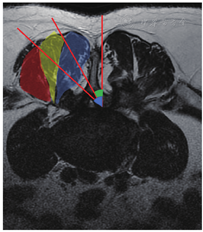

随机选取2015年在北京天坛医院骨科接受手术治疗的退变性腰椎管狭窄症患者50例,通过腰椎磁共振T2加权像轴位观察L2/3至L5/S1各节段双侧竖脊肌分束、最长肌与腰髂肋肌肌间隙。并测量侧隐窝至对侧外侧椎旁肌间隙角度α与对侧Wiltse肌间隙角度β(图1)。

50例腰椎磁共振T2加权像轴位显示L2/3至L5/S1各节段双侧最长肌与腰髂肋肌肌间隙均稳定存在。侧隐窝至对侧外侧椎旁肌间隙角度α=49°±8°;侧隐窝至对侧Wiltse肌间隙角度β=36°±5°(图1)。